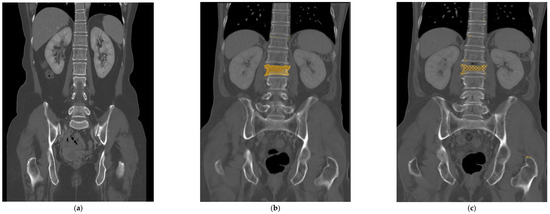

Figure 3.

As a case of false positives, the trained deep learning model color-mapped areas suspected of having fractures, but in reality, these did not have any fractures (a). However, these false positive results have a tendency to be found in the high attenuated cortex showing marginal osteophytes of the vertebra or normal endplates. In this case of a false negative, the fractured vertebra segment confirmed on the MRI was colored and trained (b), but the deep learning model could not recall a fractured segment when there was no checkered pixel (c). It appeared only as a subtle and narrow condensation zone on the CT, making it challenging to suspect a fracture even on the actual raw CT image.